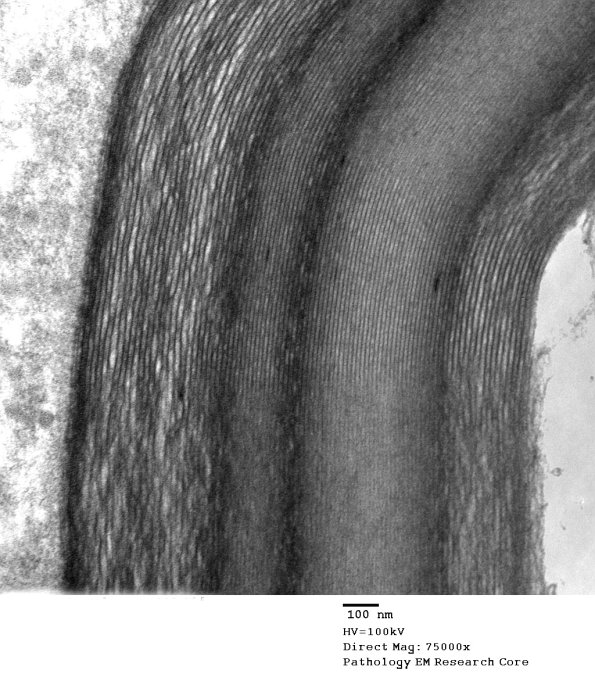

Washington University Experience | PERIPHERAL NEUROPATHY | 3 NORMAL MYELIN & SCHWANN CELLS | 1 Myelin | 7A2 (Case 7) Unusual myelin EM 005 - Copy

Higher magnification does not confirm the pattern of UCM or WSM. (electron micrograph)